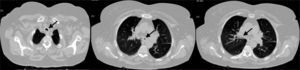

A 68-year-old female with a diagnosis of childhood asthma, was referred to the pulmonologist for recurrent episodes of acute severe dyspnoea and wheezing for the last three years. These were treated as asthma, with inhaled bronchodilators and corticosteroids, but without significant clinical improvement. She performed lung function tests, which showed a moderate bronchial obstruction, with limited response to bronchodilation. Chest CT revealed tracheal and bronchial wall thickening and luminal narrowing (Fig. 1). This tracheobronchial stenosis was also observed in bronchoscopy. In the subsequent year of follow up, she developed red eye episodes, polyarthritis, recurrent ear pain and saddle nose deformity. Autoimmunity was negative, but sedimentation rate was elevated (26mm). Relapsing polychondritis was then diagnosed, according to the criteria developed by McAdams et al.1 The patient started treatment with oral corticosteroids and methotrexate, with good clinical response. No specific treatment for tracheobronchial stenosis has yet been required. We highlight the clinical challenge of this diagnosis, due to insidious manifestations of the disease, and raise awareness of tracheobronchial involvement in relapsing polychondritis, which in some cases can lead to critical airway stenosis.2